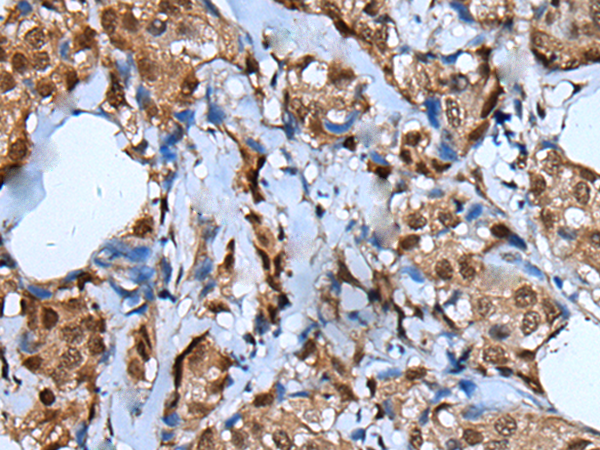

IHC positive control: |

Human breast cancer |